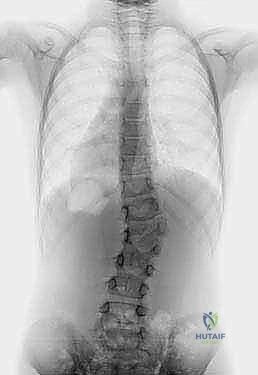

1. التصوير بالأشعة السينية (X-rays) البانورامية

يتم أخذ صور للعمود الفقري بالكامل من الأمام والخلف والجانبين أثناء وقوف الطفل (إذا كان قادراً على الوقوف). هذا يساعد في قياس زاوية الانحناء (زاوية كوب - Cobb Angle) وتحديد موقع ونوع الفقرة النصفية بدقة.